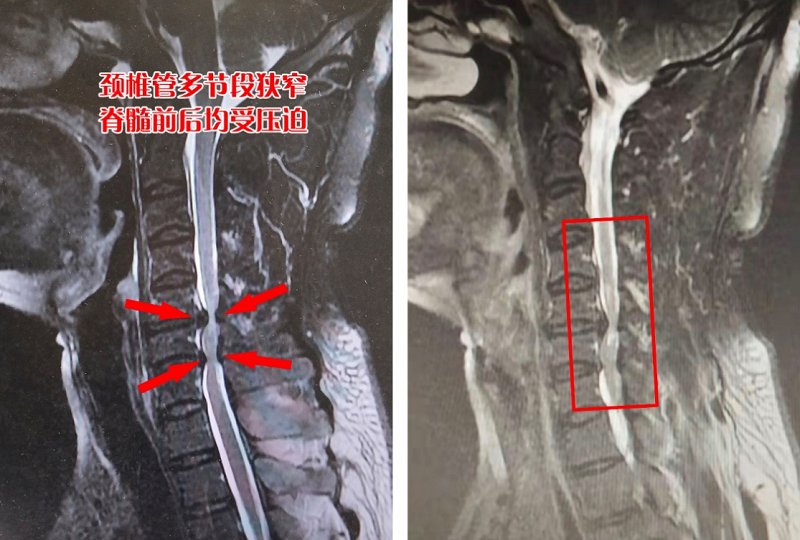

2月18日,张先生到荆门二医脊柱外科就诊。“四肢肌力减弱、感觉减退,MR显示颈椎C3-C7节段椎间盘突出,尤其是C5-C7节段颈椎管内的脊髓前后方均受压迫、损伤……”荆门二医脊柱外科主治医师万谦细致检查后,诊断为“脊髓型颈椎病”。

▲影像显示徐先生颈椎管多节段狭窄,脊髓前后均受压迫